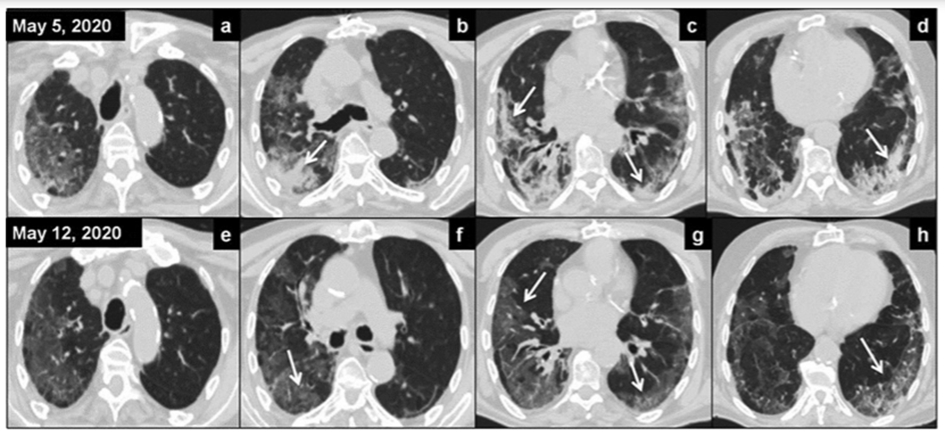

In figura 6 sunt reproduse investigatiile CT a 4 pacienti ce au fost tratati cu LDRT (1 Gy) in trialul efectuat de echipa lui Sanmamed din Spania (Int J Rad Oncol Biol Phys (noiembrie 26, 2020). Examinarile au fost efectuate inainte de iradiere si la 7 zile dupa iradierea pulmonara.

Figura 6.

In randul de sus situatia pulmonara a 4 pacienti inainte de iradiere iar in randul de jos situatia la 7 zile dupa radioterapie. Condensarile la nivelul parenchimului pulmonar (indicate prin sagetile albe) prezente la inceput sunt mult reduse la 7 zile dupa radioterapie.